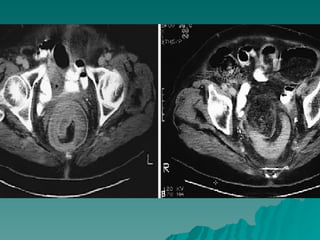

 TAC

CANCER DE COLONY RECTO DIAGNOSTICO  Historia clínica.  Exploración física ( tacto rectal ).  Laboratorio clínico y Rx. tórax, MT ( ACE ).  Colon por enema.  Colonosocopia ( biopsia ).  TAC  Ultrasonido endoluminal.